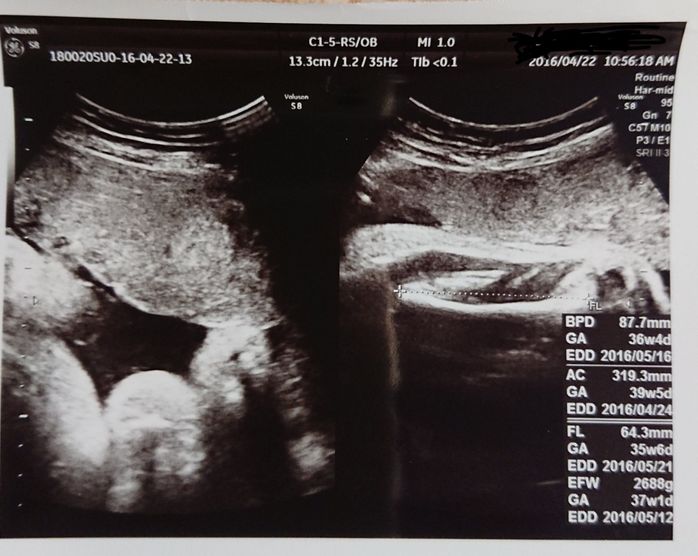

妊娠37週目 いよいよ近づく出産を前に

大きくなりすぎてエコー写真ではよくわかりません。体重は、妊娠してから9kg増加。予定日が近づいて、楽しみな気持ちと不安な気持ちが入りまじります。臨月に入り、お腹はパンパンで歩くのも大変。予定日の1週間位前には、いつ陣痛がくるのか毎日ドキドキして過ごしていました。